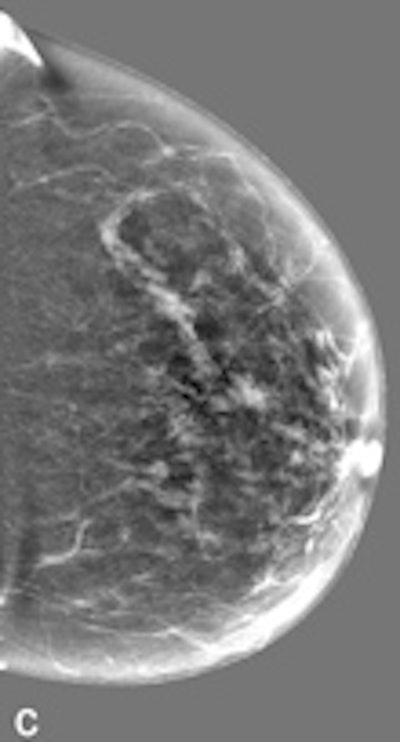

| Example of a subtle finding in a right-sided mediolateral oblique view, which was only reported by radiologists when using premium view (PV). A: Digitized prior. B: Tissue equalization (TE) processed image. C: PV processed image with the annotation. D: The resulting image of subtracting TE from PV. E: Thresholded version of D. White areas indicate that pixels in the PV image have relatively higher intensity than the related pixels in the TE image, whereas black areas indicate the opposite. In PV images, low-frequency trends are suppressed (no noticeable signal decrease in the breast edge in PV compared with TE), whereas higher-frequency structures are emphasized (e.g., glandular structures). All images courtesy of Wouter Veldkamp, PhD, Leiden University Medical Center. |

The cases were acquired using the Senographe Essential digital mammography system (GE Healthcare). Tissue equalization is a standard GE application that corrects for low-frequency variations resulting from under- and overpenetration of x-rays. As a result, the image dynamic range is reduced, enabling improved soft-copy image display.

The local contrast optimization, premium view, has been designed to improve the quality of the information presented to the radiologist for diagnosis and also the reading speed by optimizing the local contrast in breast structures. In premium view, low-frequency structures are obtained from the original image by low-pass filtering. High-frequency structures are obtained by subtracting the low-pass filtered image from the original image. The low- and high-frequency images are both processed and weighted individually, then added together. The resulting image exhibits reduced contrast between different tissue types but enhanced contrast of small-scale anatomical architecture.

Another example of a finding in a left-sided craniocaudal view that was reported clearly more often by radiologists when using premium view (PV). A: Tissue equalization (TE) processed image. B: PV processed image with the annotation. C: Similar to image above, the resulting image of subtracting TE from PV. D: The thresholded version of C.For all six radiologists, perceived case suspiciousness -- defined as the highest probability of malignancy of all radiologist findings -- was higher using premium view optimization.

The major difference between the processing algorithms was an additional local contrast optimization when premium view was applied. "Premium view is aimed at increasing the visibility and suspiciousness of malignant lesions, but in our study the perceived suspiciousness of benign lesions and normal cases is increased as well," the researchers wrote. "An effect of local contrast enhancement could be that both normal (dense) structures and abnormal structures appear more suspicious due to their enhanced signal."